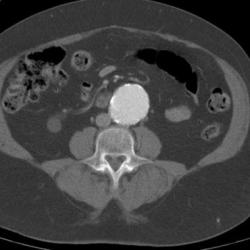

Abdominal aortic aneurysms (AAAs) are relatively common and are potentially life-threatening. Aneurysms are defined as a focal dilatation in an artery, with at least a 50% increase over the vessel’s normal diameter. Thus, enlargement of the diameter of the abdominal aorta to 3 cm or more fits the definition.

Abdominal aortic aneurysms (AAAs) are relatively common and are potentially life-threatening. Patients at greatest risk for AAA are men who are older than 65 years and have peripheral atherosclerotic vascular disease. See the image below.